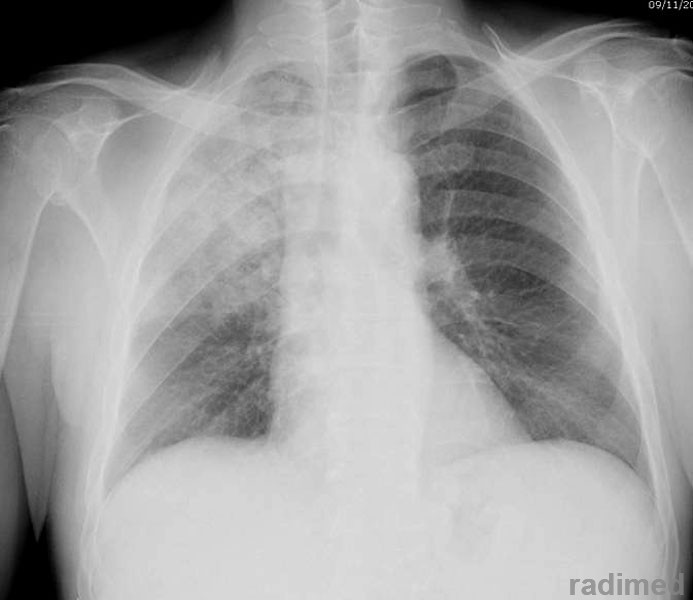

Nuevas guías para neumonía intrahospitalaria proponen acortar la duración del tratamiento

15 julio 2016

IDSA & ATS, 14 de julio de 2016